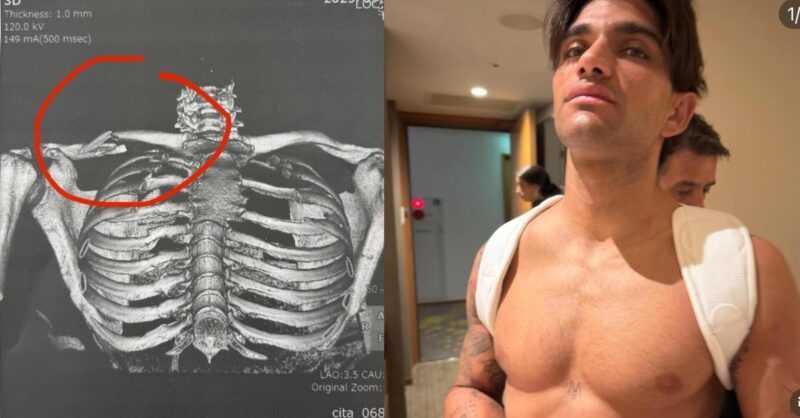

Le scénario est brutal : Martin, trop optimiste sur les freins dès le premier tour, perd le contrôle de sa moto et percute Marco Bezzecchi, provoquant une chute spectaculaire. Verdict : fracture ouverte de la clavicule droite, nouvelle opération à subir, et un coup dur pour un pilote déjà sur la corde raide physiquement.

Sur les réseaux sociaux, l’Espagnol tente de rester fidèle à son image de guerrier.

« Ça fait mal… mais tu sais qui je suis. Tu ne me verras jamais abandonner. À bientôt ! »

Il a publié la radio de sa clavicule brisée, deux photos de lui après les premiers examens, ainsi qu’un message tendre adressé à sa compagne et à son père. Mais derrière la façade combative, l’inquiétude grandit. Martinator semble rattrapé par une réalité : celle d’un corps qui encaisse coup sur coup.